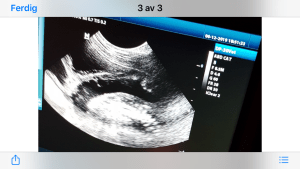

Ultralyd drektighet katt